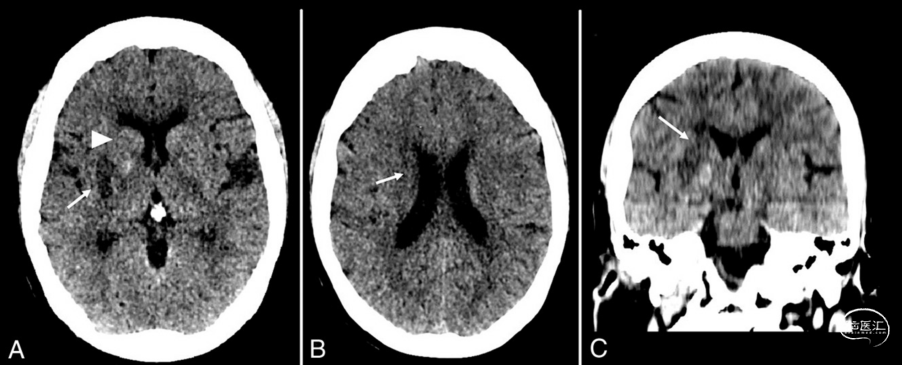

基于CTP成像的双侧大脑内静脉和丘脑静脉的时间衰减曲线测量脑血流达峰时间(TTP)和峰值强度(采用Hounsfield为单位),并计算缺血侧和正常侧之间的TTP差异(ΔTTP = TTP缺血半球–TTP正常半球)和峰值强度的相对减少量(增强缺血大脑半球–增强正常大脑半球/增强正常大脑半球)(图1)。所有患者在取栓术后24(SD,±12)小时进行的NCCT检查确定尾状核头部、尾部,豆状核和内囊的组织灌注命运(图2)。纹状体内囊缺血定义为梗死和损伤,即梗死、CT对比增强或缺血区域内出血性转化的区域≥1个。此外,计算纹状体内囊缺血评分,0:无缺血区,1:1个缺血区,2:≥2个缺血区。

图2. 大脑中动脉M1段闭塞患者取栓术后NCCT扫描。A:壳核梗死,B:尾状体梗死,C:内囊梗死。